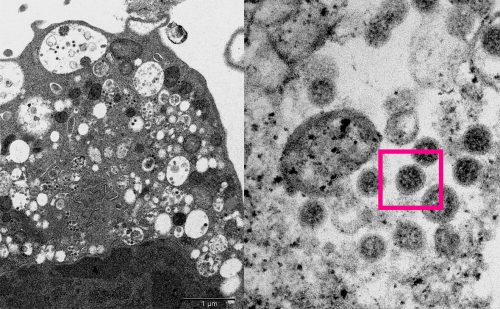

Новую разновидность коронавируса обнаружили в ЮАР и Ботсване в конце ноября. Ученые выяснили, что штамм мутации в S-белке, что позволяет ему быть более заразным и лучше обходить иммунную защиту организма, в том числе у привитых людей. Изначально сообщалось, что вирус-мутант мог возникнуть в организмах людей с ВИЧ или СПИД. По другой версии, «омикрон» появился в 2020 году сначала у грызунов, которые могли заразиться коронавирусом от людей, а потом он снова вернулся к человеку.